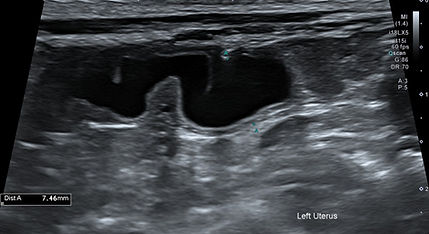

초음파

Ultrasound / Echocardiography

초음파 검사는 신체에 무해한 고주파 음파를 이용해 내부 장기와 조직을 실시간으로 영상화하여 관찰하는 비침습적 진단 검사입니다.

복부초음파

Abdominal Ultrasound

복강 장기 (간, 담낭, 비장, 신장, 부신, 방광, 위장관, 췌장, 생식기계 등) 실질의 이상 소견과 혈관 이상을 평가할 수 있으며,

혈액 검사 및 방사선 검사만으로는 명확히 확인되지 않는 각종 질환에 대한 감별에 유리합니다.

또한, 초음파 유도 하에 안전하게 세침흡인검사 및 복수/흉수/심낭수 천자가 가능합니다.

본원에서는 환자의 안정을 최우선으로 하여, 숙련된 영상 전공 수의사가 조용하고 독립된 검사실에서 세심하게 검사를 진행합니다.

위종양

만성신장질환

방광염

장염

자궁수종